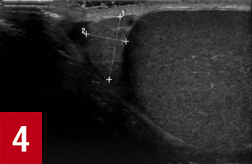

At 4 hours after the onset of pain, testicular ultrasonography was performed in view of the persistent mild left testicular tenderness noted during the initial examination. The results revealed left testicular torsion with an absence of blood flow to the left testis (Figures 1-5). The scrotal skin was of normal thickness with no hyperemia. The testis demonstrated normal size and echogenicity, but the epididymal head was enlarged and ill-defined, with prominent cystic features indicative of infarction. A small hydrocele was also present. The spermatic cord was normal, with no signs of torsion in the inguinal canal.

Figure 4: Right epididymis was normal in size and echogenicity.